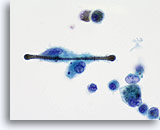

Figure 155

Ferruginous Body

Fibers of asbestos, or other minerals may be coated with ferroprotein creating a “ferruginous body”. This structure is partially engulfed by a macrophage.

Ferruginous Body

Fibers of asbestos, or other minerals may be coated with ferroprotein creating a “ferruginous body”. This structure is partially engulfed by a macrophage.

Figure 155

Ferruginous Body

Fibers of asbestos, or other minerals may be coated with ferroprotein creating a “ferruginous body”. This structure is partially engulfed by a macrophage.

Ferruginous Body

Fibers of asbestos, or other minerals may be coated with ferroprotein creating a “ferruginous body”. This structure is partially engulfed by a macrophage.